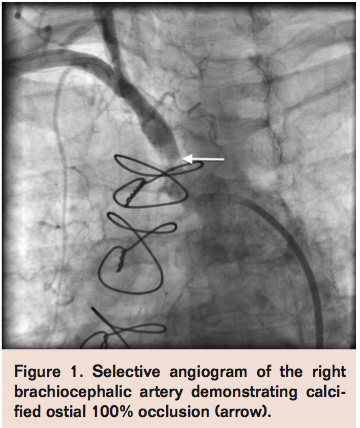

Fluoroscopy of the aortic arch revealed a heavily calcified porcelain arch. Right brachiocephalic artery angiogram revealed heavily calcified 100% ostial occlusion (Figure 1). At this point, the decision was made to intervene on the right brachiocephalic artery occlusion in the setting of symptomatic disease.